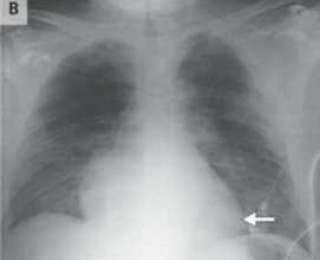

Сделав пациенту рентген грудной клетки и компьютерную томографию, медики выяснили, что его сердце перевернулось на 90 градусов и переместилось в правую часть груди. Они также отметили, его аорта и легочная артерия была повернута вправо.

Мужчина также получил многочисленные переломы ребер, коллапс легкого, синяки на обоих легких и разрыв селезенки. Тем не менее, несмотря на все полученные травмы, он оставался в сознании. Единственным признаком проблем с сердцем было небольшое падение кровяного давления и небольшое увеличение его частоты сердечных сокращений.